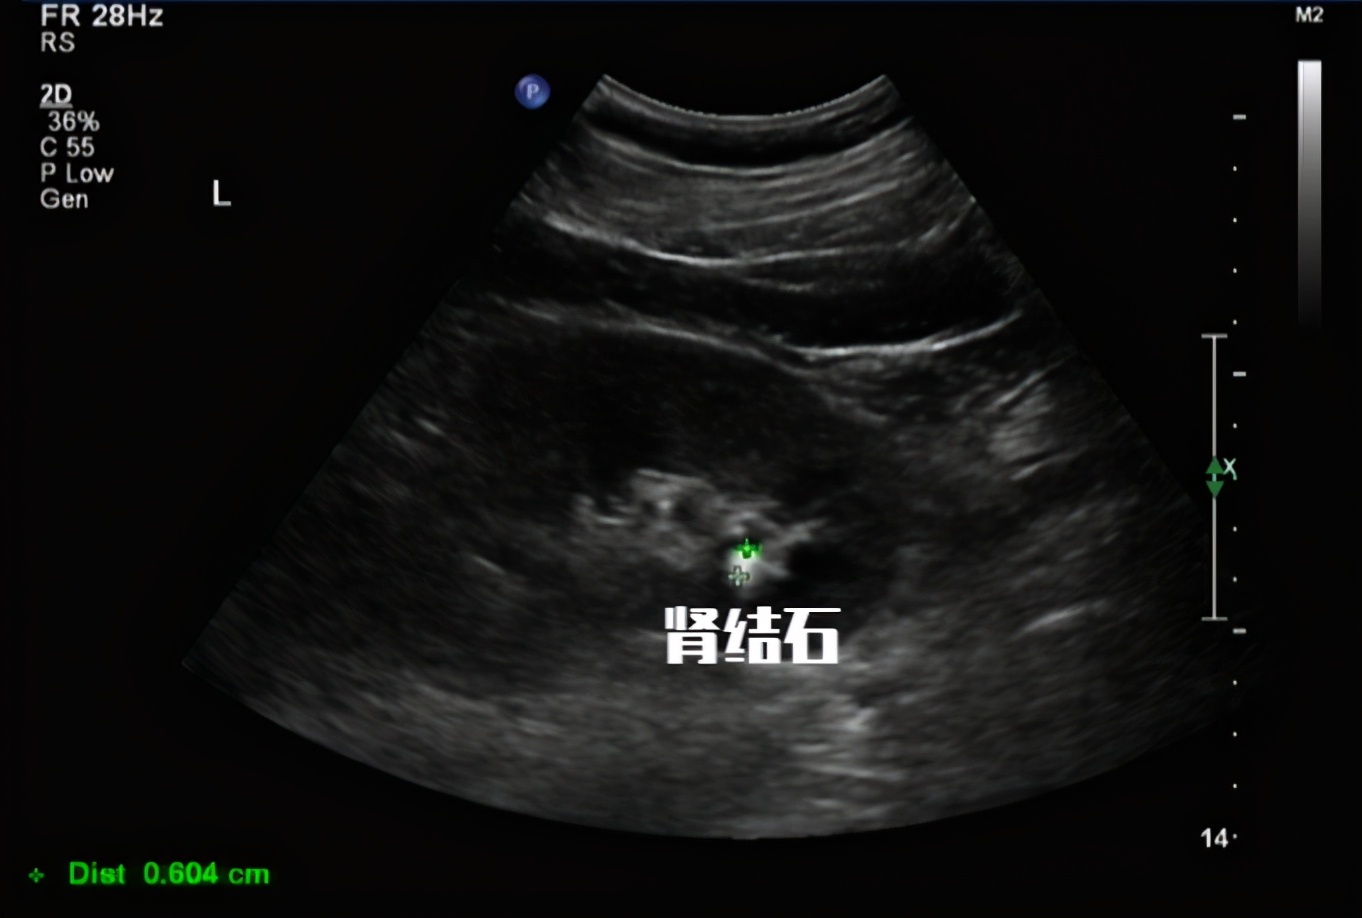

尿隐血阳性: 常见于肾脏或尿道疾病、肾性高血压、尿路结石、肾结核、恶性肿瘤、血红蛋白尿症(不同血型输血、溶血性贫血等)、肌红蛋白尿症(骨骼肌破坏)。